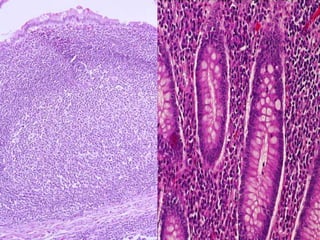

Son agregados de nodulos

linfoides encapsulados de

manera incompleta, que

protegen la entrada a la

faringe bucal.

Están en íntima relación con

una membrana epitelial

húmeda.

Se caracterizan por presentar

depresiones del epitelio

superficial.

Se localizan entre los arcos palatogloso y

palotofaríngeo.

Epitelio plano estratificado no queratinizado.

El parenquima se compone de multiples nódulos

linfáticos

Cápsula delgada de tejido conectivo denso irregular.

Glándulas mucosas cuyos conductos pueden

desembocar en el fondo de las criptas.

Se encuentran en la superficie dorsal del

tercio posterior de la lengua.

Cada amígdala posee una cripta, cuya base

recibe los conductos de las glándulas salivales

menores mucosas